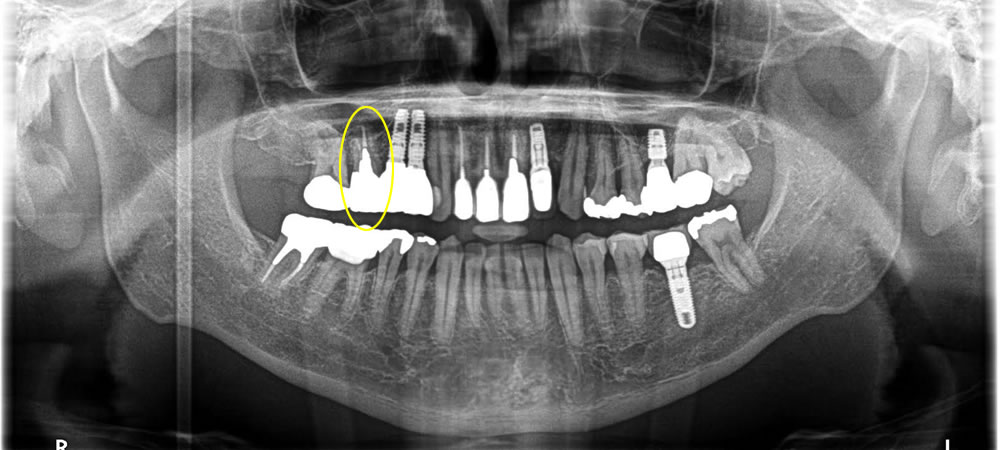

入れ歯とオールオン8による全顎治療の症例

年齢

50代

性別

男性

症例を見る

痛む歯を抜歯してインプラントで治療した症例

40代